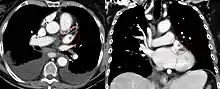

The left atrial appendage can be seen on a standard posteroanterior X-ray, where the lower level of the left hilum becomes concave.[10] The left atrial appendage can serve as an approach for mitral valve surgery.[11] The body of the left atrial appendage is anterior to the left atrium and parallel to the left pulmonary veins. The left pulmonary artery passes posterosuperiorly and is separated from the atrial appendage by the transverse sinus.[12] With certain conditions, the left atrial appendage may be associated with risks of stroke from blood clot formation, because of which surgeons may choose to close it during open-heart surgery.[13]